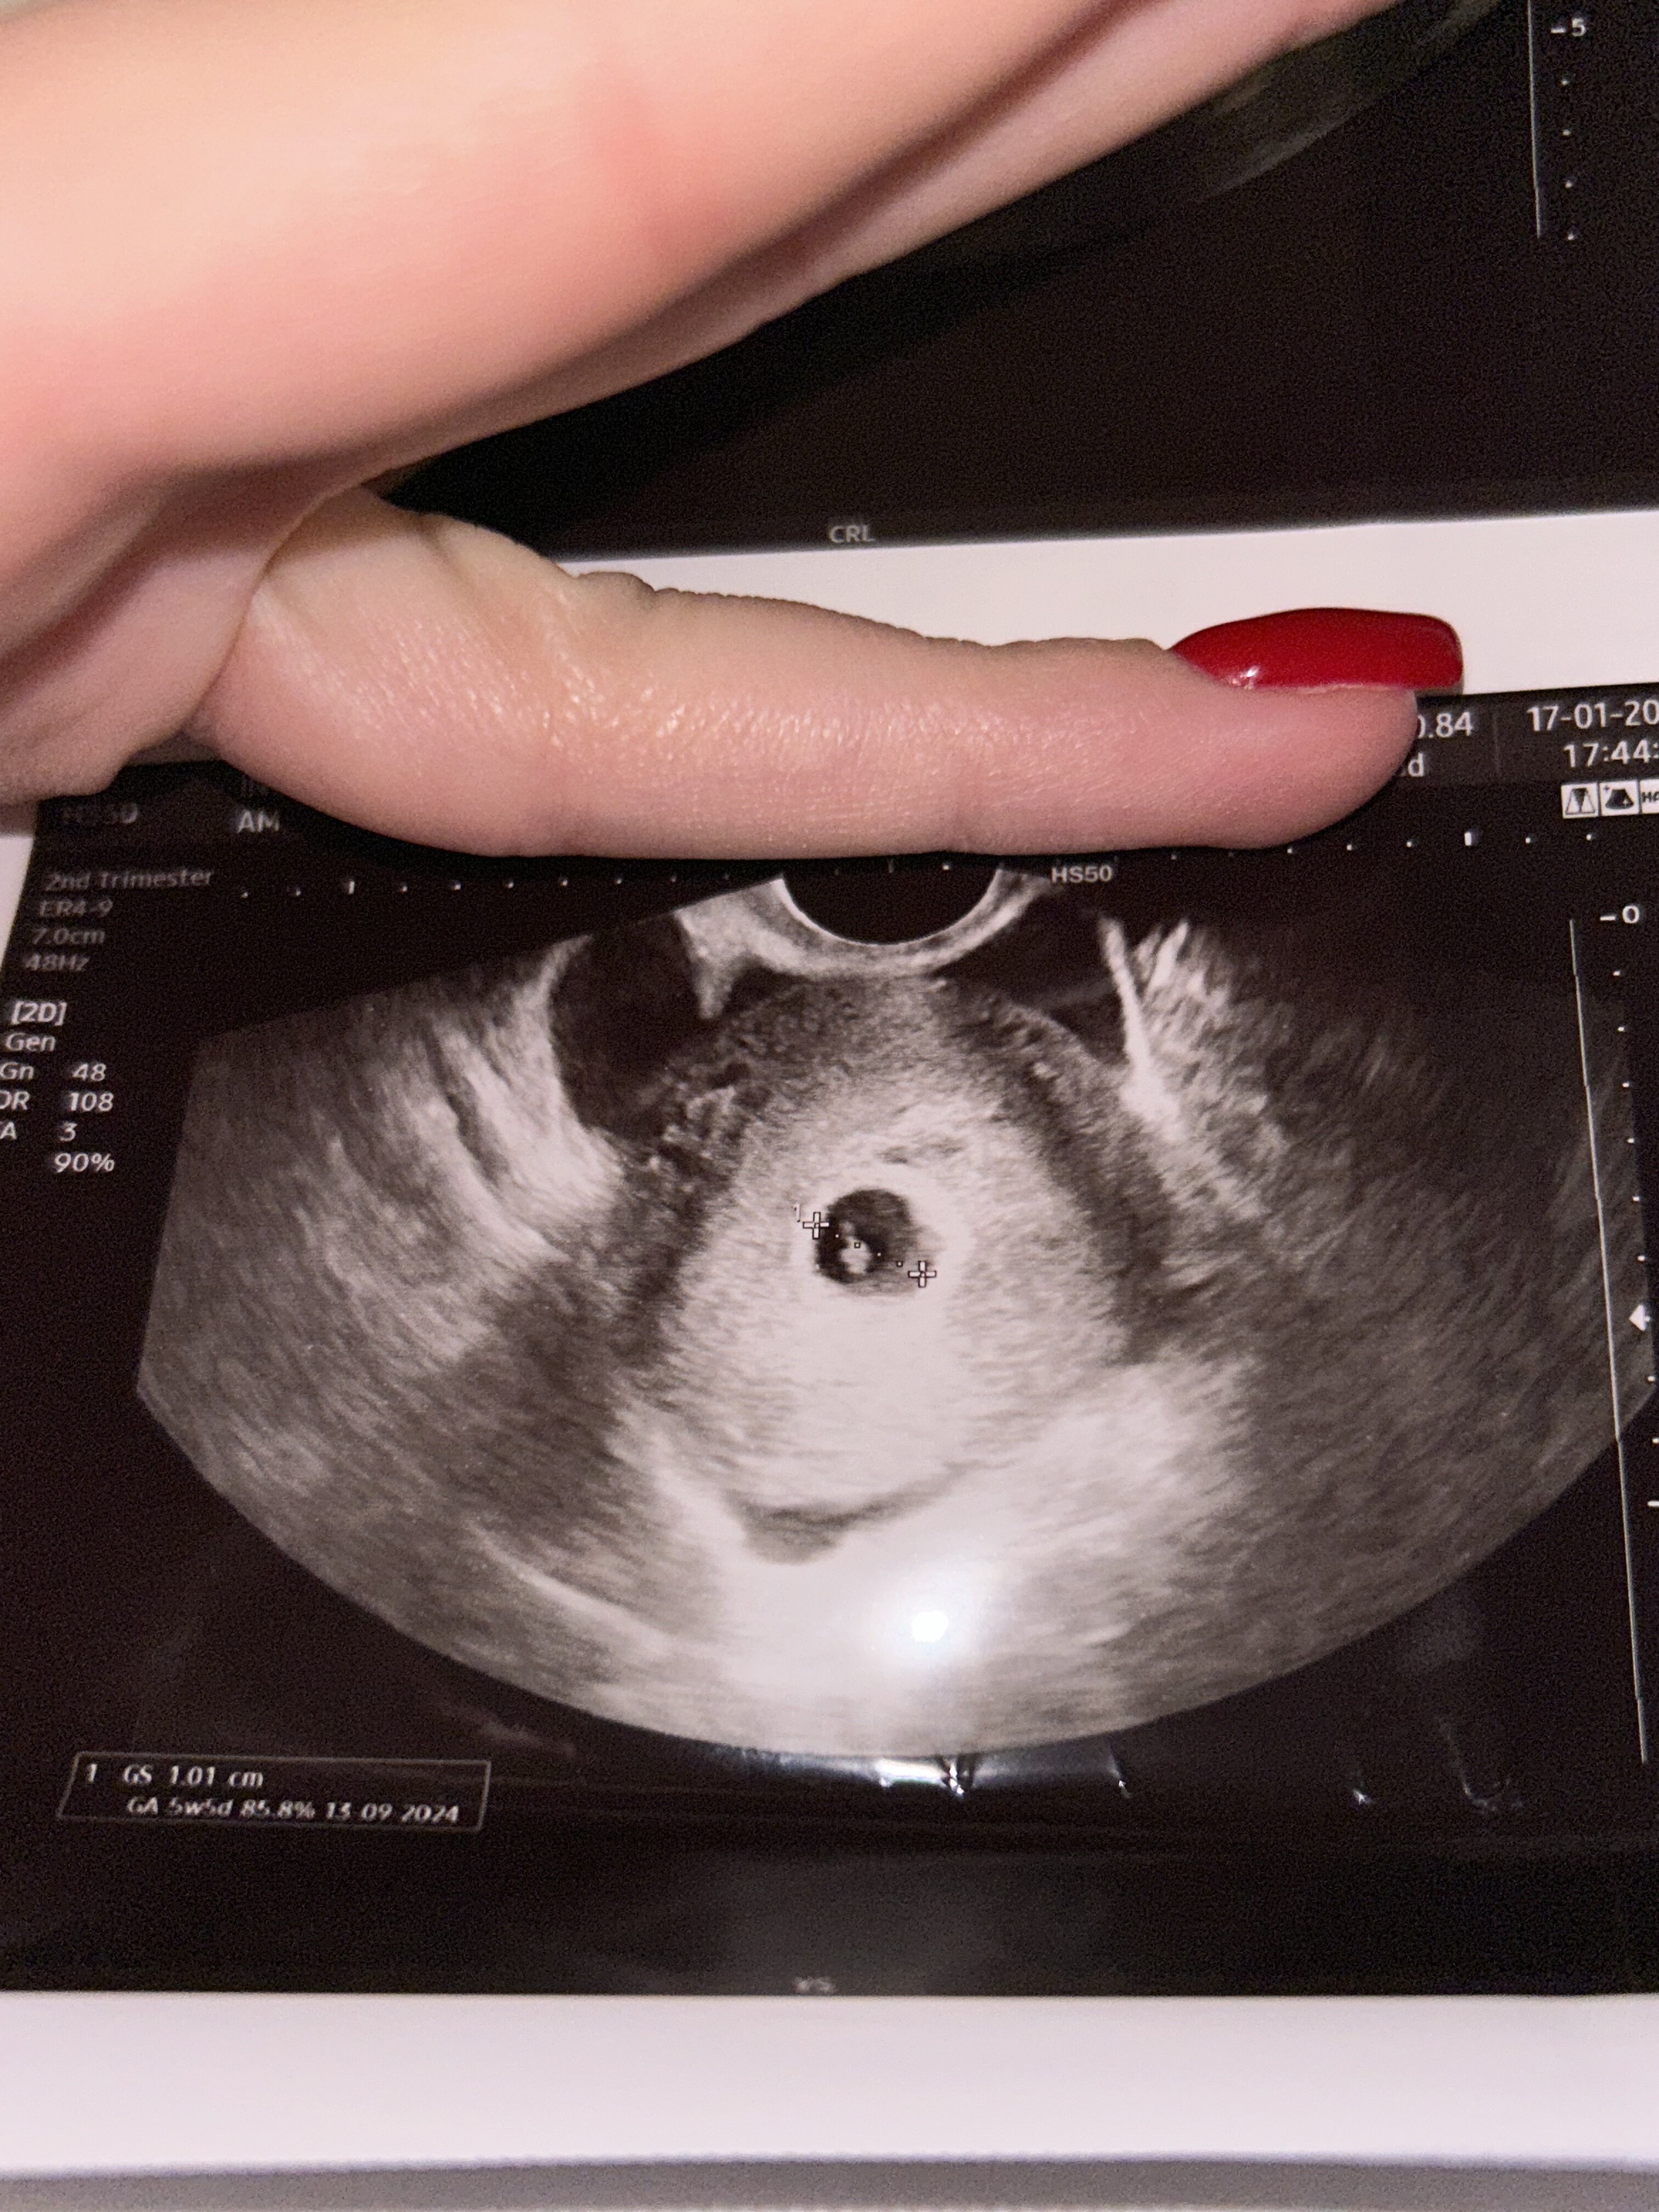

Zdjęcie usg

Hej ! Jestem w ciąży . Byłam wczoraj u ginekologa pierwszy raz według GS pęcherzyk 10mm 5tyg 6dni, a według OM: 4w6dni, niestety nie slychac jeszcze echa zarodka 😔 lekarz zalecił przyjechać tydzień później , natomiast na zdjęciu USG widać coś w pęcherzyku i zastanawiam się co to jest, w podekscytowaniu i rozmowie na różne tematy nie zdążyłam zapytać lekarza, czy ktoś powie mi czy to zarodek? Ciałko żółte? Czy może jakies prześwietlenie światła? Czy wgl jest szansa że serduszko zabije? Trochę się stresuje . Pozdrawiam

• 1A9A3DD8-D7D9-4114-A2E9-C79070D2086B.jpeg

1A9A3DD8-D7D9-4114-A2E9-C79070D2086B.jpeg

1,6 MB · Wyświetleń: 432